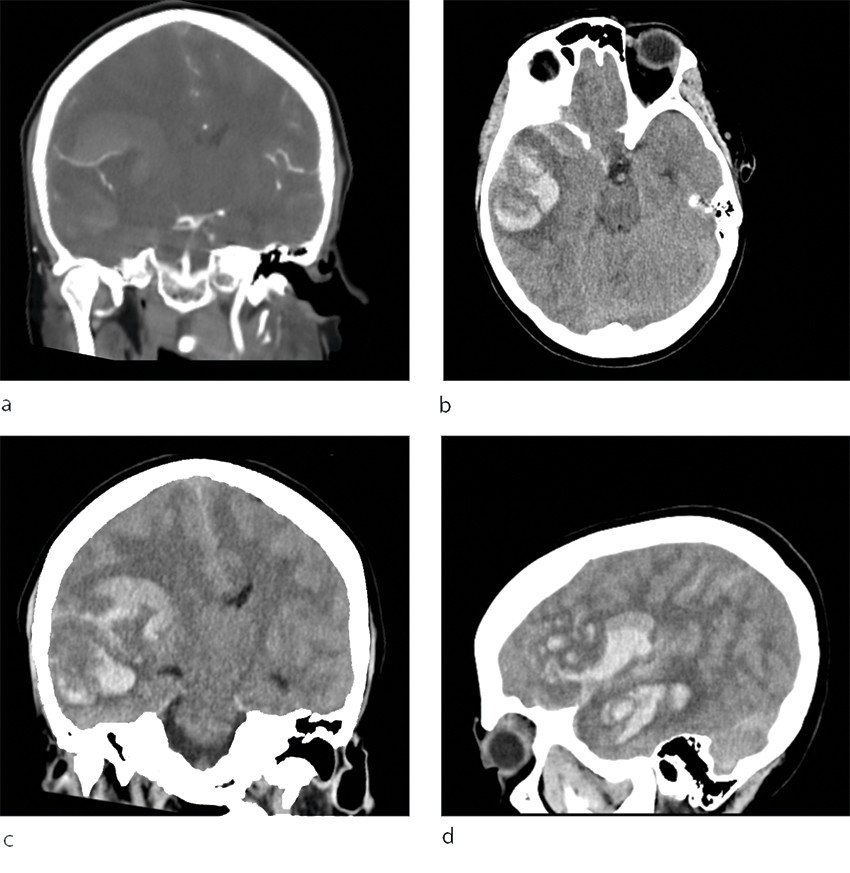

Det var sterk mistanke om intracerebral blødning, og slagalarmen ble utløst. CT caput ble rekvirert og viste en stor høyresidig intracerebral blødning temporoparietalt i forsyningsområdet til arteria cerebri media, utviklende ødem med overskyting av midtlinjestrukturer og kraftig kompresjon av høyre sideventrikkel. Det var både subaraknoidalt blod og en del ferskt blod i hjerneparenkymet (figur 1), men det var ikke synlig blod i ventrikkelsystemet. CT angiografi var uten funn av aneurisme.

Få dager etter denne hendelsen ble det meldt fra Rikshospitalet om flere tilfeller av alvorlige blodpropper og blødninger hos pasienter som hadde fått identisk vaksine. Også disse pasientene hadde lave trombocyttall, og i disse tilfellene klarte man å finne en sammenheng mellom hendelsene og vaksinen (1). Tilstanden er etter dette omtalt som vaksineindusert trombotisk trombocytopeni (VITT), som kjennetegnes av lave trombocyttall, trombedannelser og antistoff mot platefaktor 4 (1, 5). I lys av denne kunnskapen ble det gjort nye undersøkelser, og man fant også hos vår pasient tendens til trombedannelse med små tromber i sinus transversus, pannelapper og a. pulmonalis. Det ble også påvist antistoff mot platefaktor 4. Samlet sett er det derfor mye som taler for at dette var et tilfelle av vaksineindusert trombotisk trombocytopeni. Retrospektivt må man spørre seg om blødningen sett på CT representerte et venøst hemoragisk infarkt tilsvarende det som ble sett hos flere pasienter på Rikshospitalet (1), og om blødningskomponenten kan ha vært dominerende som følge av vaksineindusert trombotisk trombocytopeni. Et venøst infarkt kunne kanskje forklare pasientens hodepine.